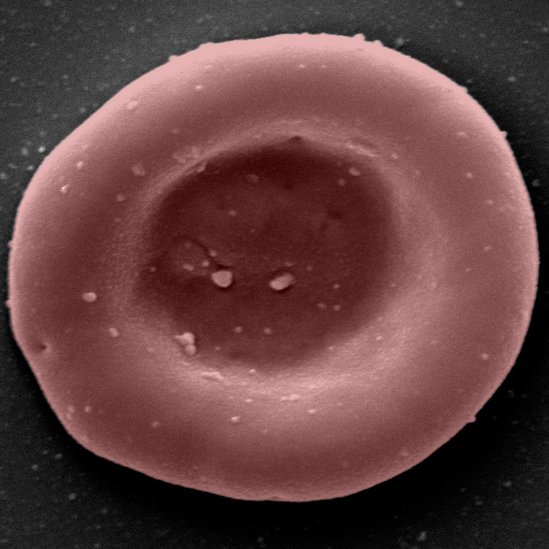

Este proyecto de investigación combina equipos en Bristol, Cambridge, Londres, y de la unidad de sangre y donaciones del servicio británico de salud (NHS, por sus siglas en inglés). Su enfoque son los glóbulos rojos que transportan oxígeno desde los pulmones al resto del cuerpo.

- Se utilizan campos magnéticos para extraer células madre flexibles que son capaces de convertirse en glóbulos rojos. Se estimula el crecimiento de estas células madre en grandes cantidades en los laboratorios y luego las guía para que se conviertan en glóbulos rojos.

- El proceso toma cerca de tres semanas y, de un grupo inicial de alrededor de medio millón de células madre, se producen 50.000 millones de glóbulos rojos.

- Estos se filtran para obtener alrededor de 15.000 millones de glóbulos rojos en la etapa adecuada de desarrollo para el trasplante.